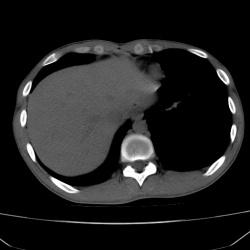

Женщина с СД 2 типа, поступила с жалобами на лихорадку, выраженную слабость. Кретинин под 300, вспалительная кровь. Выполнено КТ, до и после курса антибактериальной терапии, изменения в...